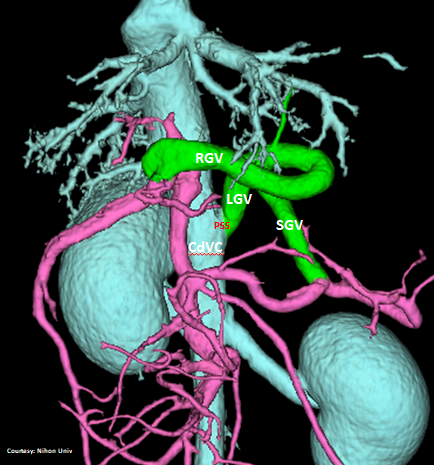

PRE-HEPATIC ENTRANCE

(GSV present)

“LGC +RGV +SGV”

Left Gastro-Caval Shunt with Right Gastric Vein and Short Gastric Vein contributions

Courtesy: Nihon Univ